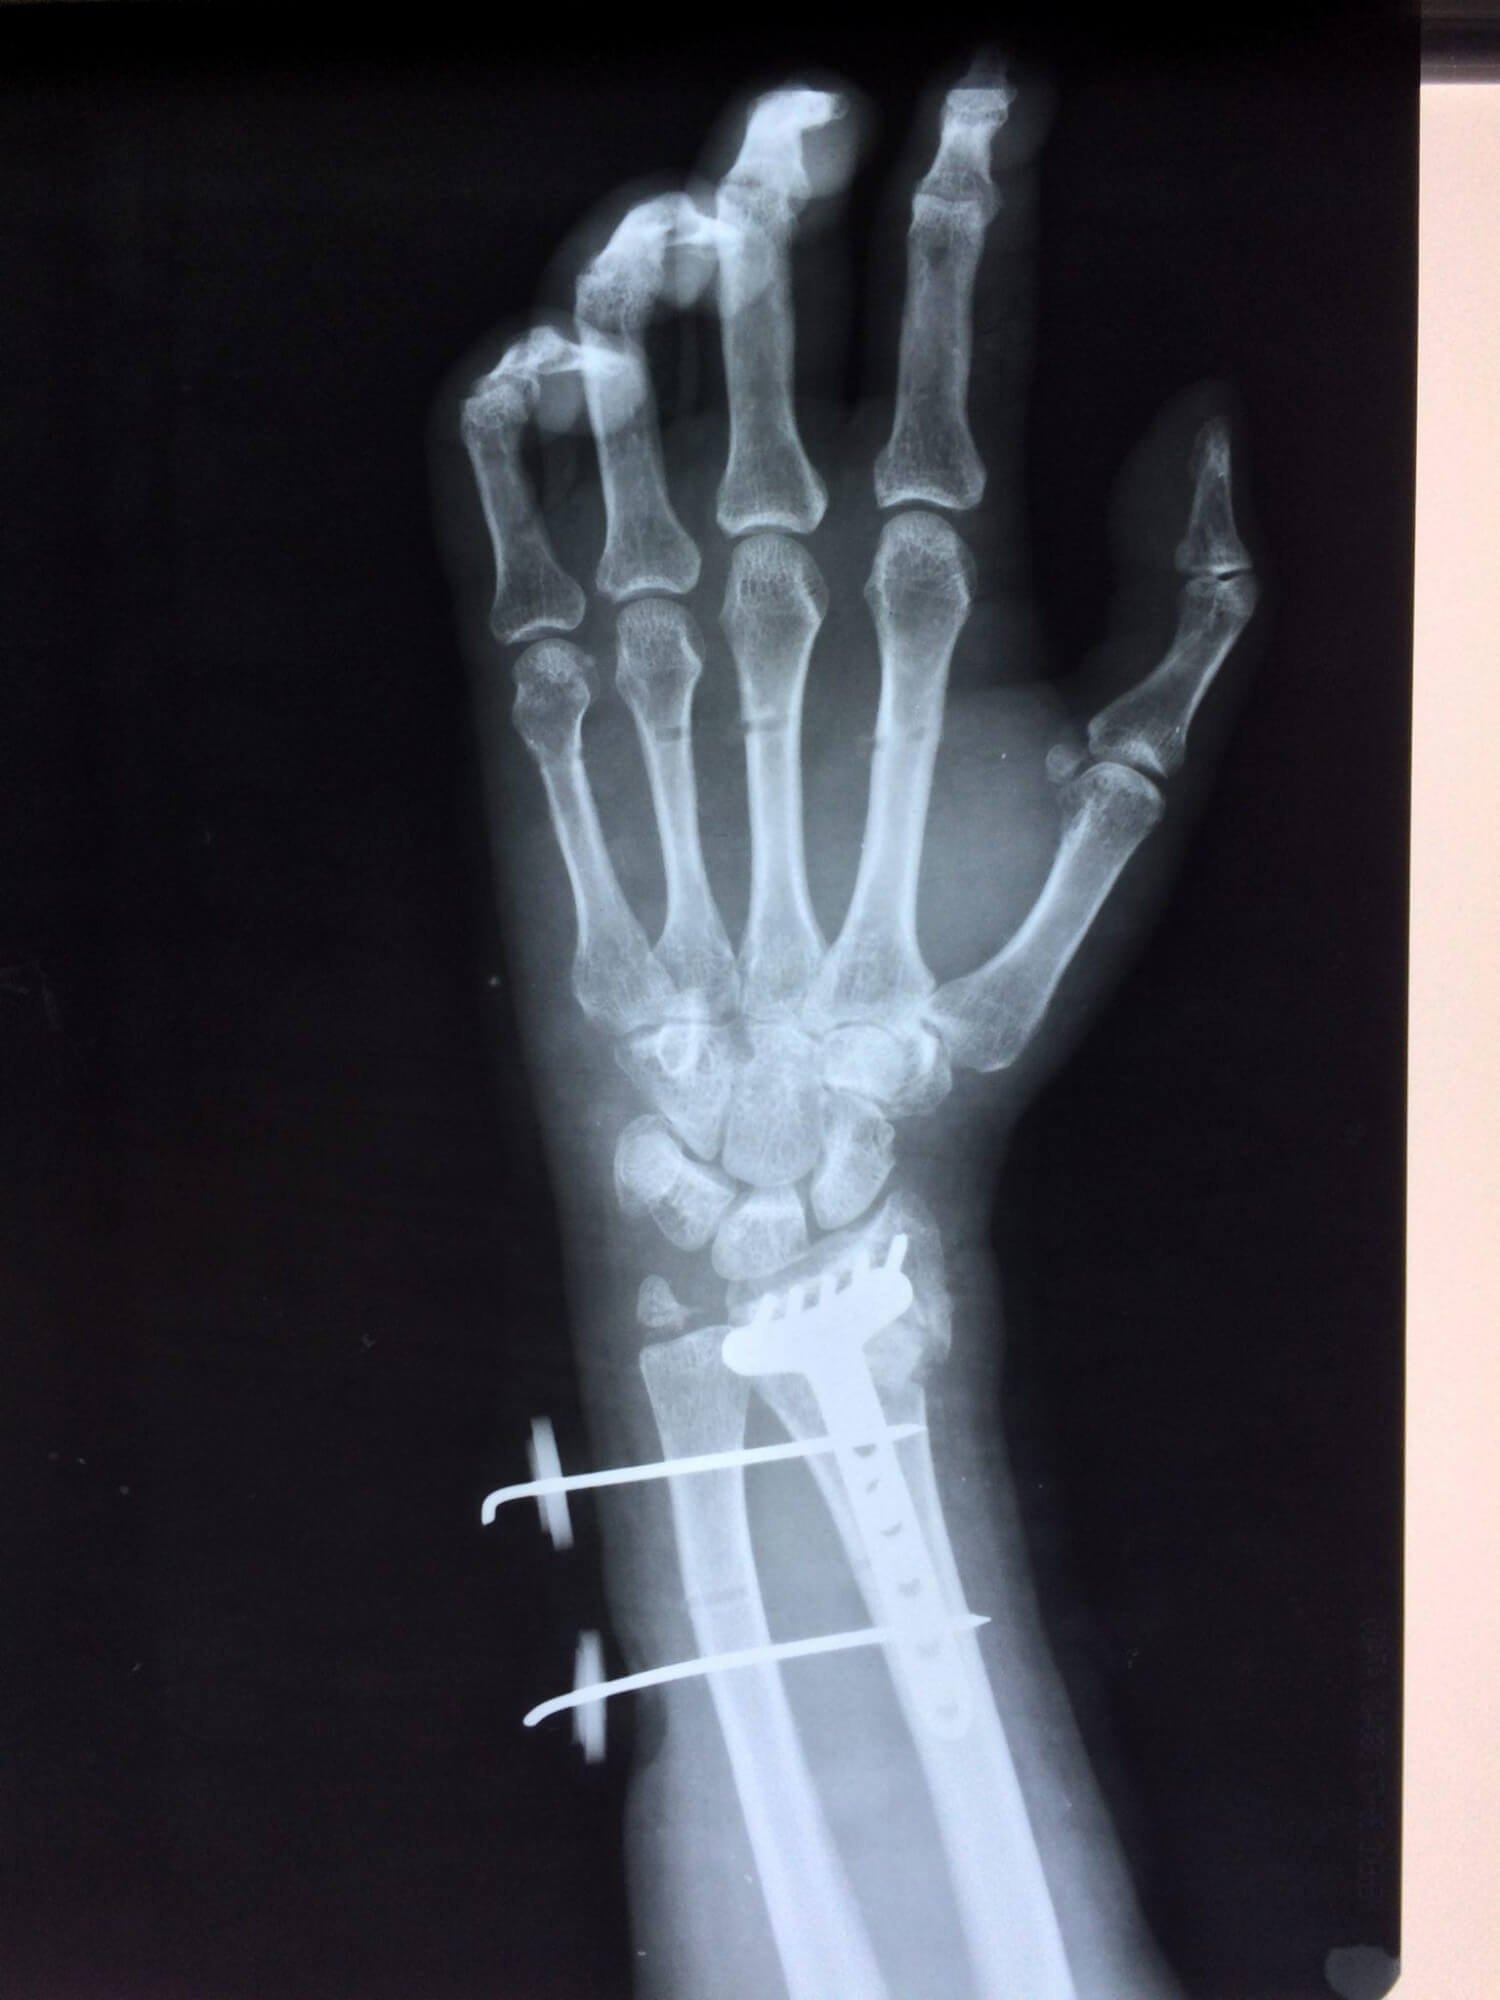

Операция - открытая репозиция, остеосинтез лучевой кости пластиной с костной ксенопластикой материалом "Остеоматрикс". На контрольных снимках в три месяца имеется консолидация перелома, миграции фиксатора нет, имеется остеоинтеграция ксенопластического материала.

Отдаленные результаты через 3 (три) месяца: